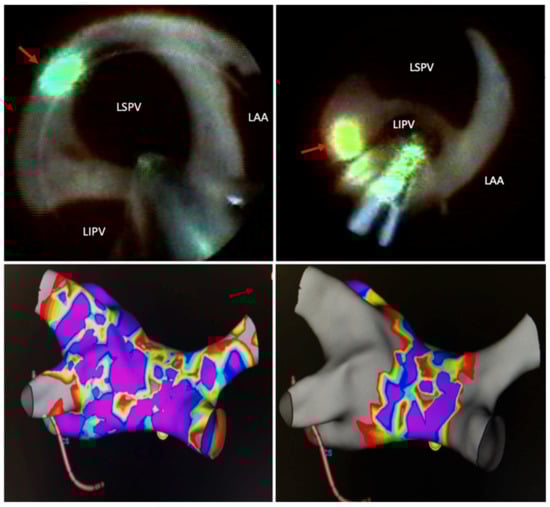

4. Lesion Generation

5. Technology Development and Technique Modification

7. Comparisons to Other Techniques